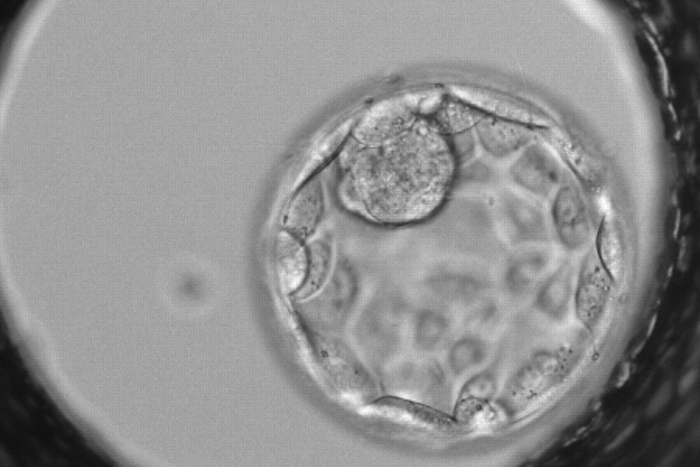

Студенты Сеченовского университета создали уникальную систему анализа эмбрионов для ЭКО

Студенты Сеченовского университета создали

уникальную систему анализа эмбрионов для ЭКО